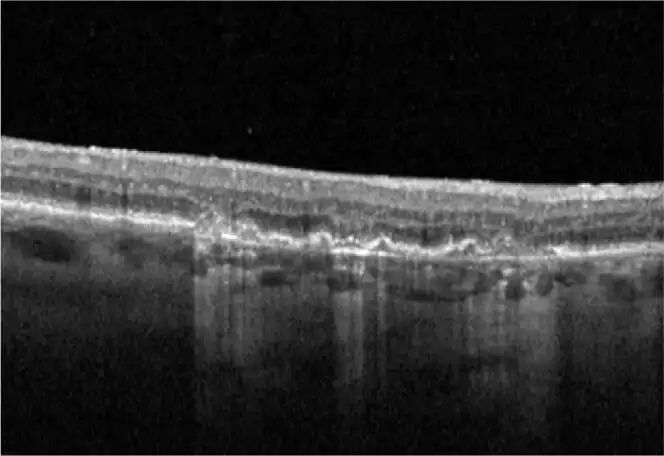

Neovascular AMD

- In clinical trials, use of IZERVAY was associated with increased rates of neovascular (wet) AMD or choroidal neovascularization (7% when administered monthly and 4% in the sham group) by Month 12. Over 24 months, the rate of neovascular (wet) AMD or choroidal neovascularization in the GATHER2 trial was 12% in the IZERVAY group and 9% in the sham group. Patients receiving IZERVAY should be monitored for signs of neovascular AMD.